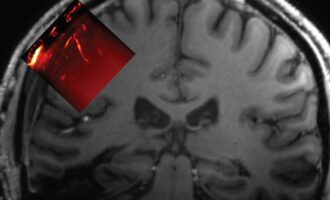

مغز

مغز انسان، ماشینی پیچیده است که درباره اش، کم می دانیم، خیلی کم اما با این حال چیزهایی می دانیم. مثلا اینکه انسان چند درصد مغز خود را به کار می گیرد؟ یا اینکه اصولا مغز چگونه کار می کند؟ و حقایقی دیگر درباره مغز.